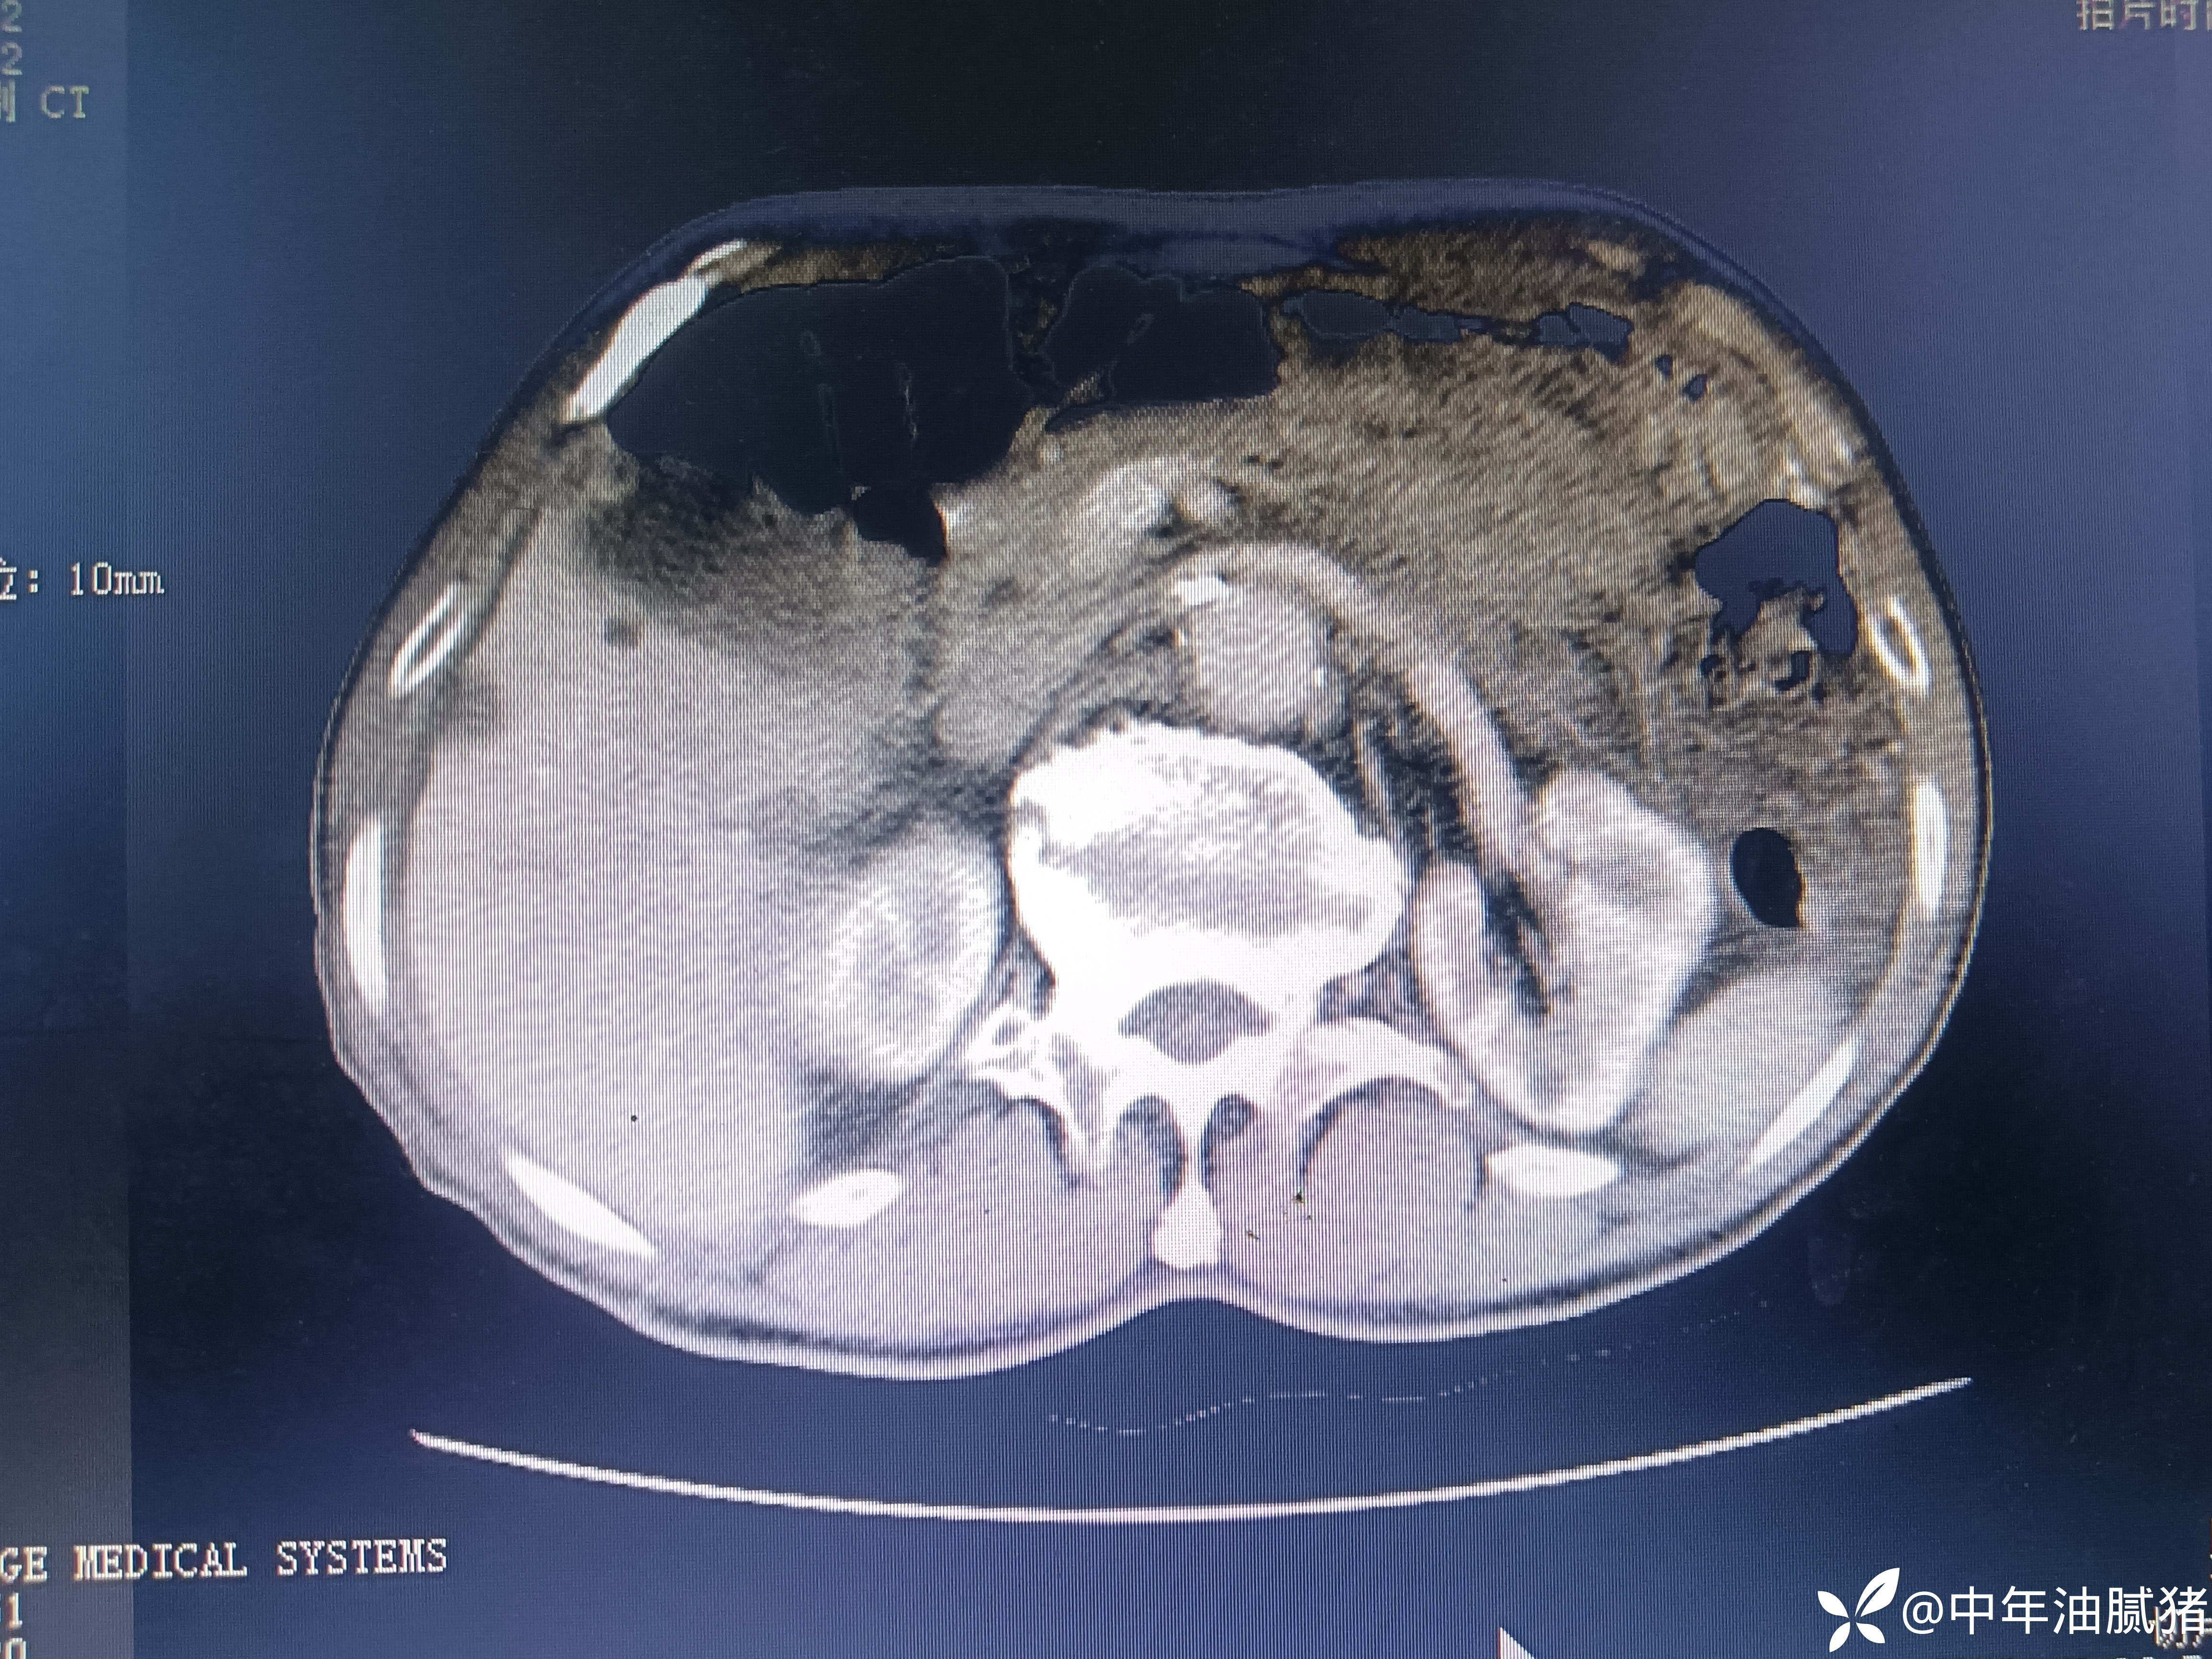

肺ct看到肝内病灶,行增强检查

建议增强ct.报告如下

考虑肝囊肿?让他走?

看后,我隐隐约约觉的不是肝囊肿那么简单?元芳,你怎么看?狄阁老,我也是这么认为!摇人,掏起手机:喂,w主任,请帮我看看这个ct。5分钟后报告修改如下